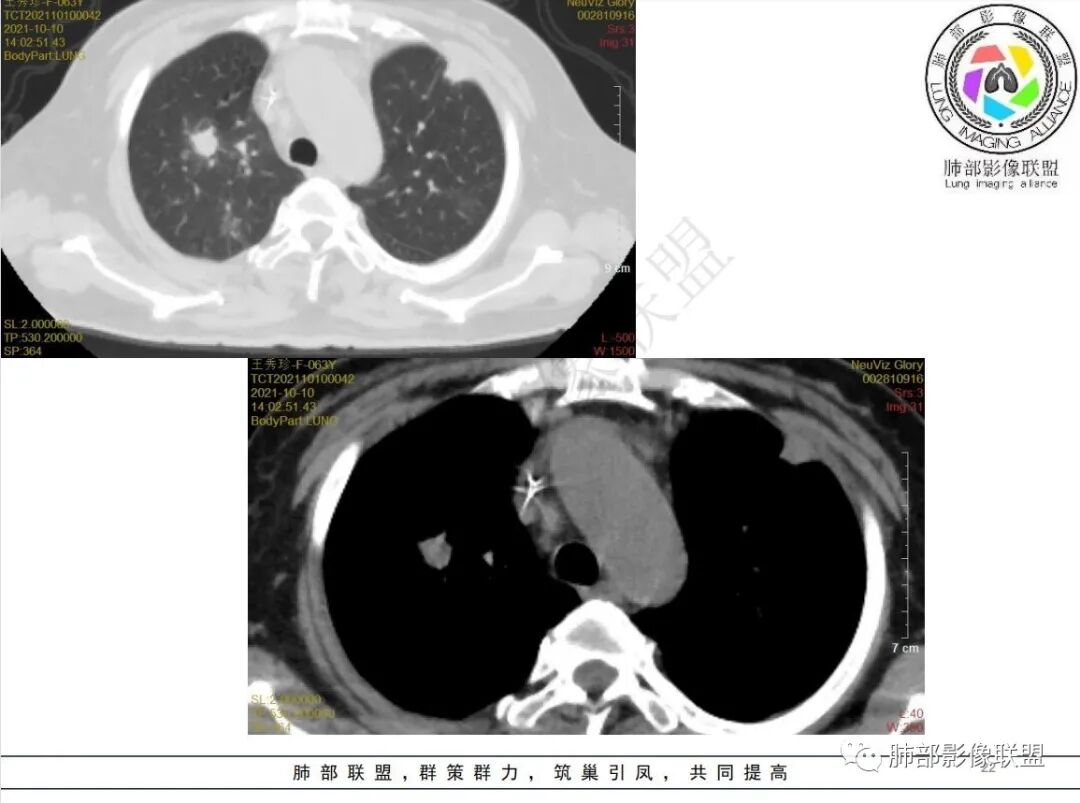

白血病化疗后,多发结节、胸膜下楔形影、反晕,大血管受侵,结合用药,考虑毛霉

白血病化疗后,出现多发结节,边缘可见晕征,病灶内可见多发坏死,右肺中叶肺动脉可见充盈缺损,右肺中叶可见融冰征,考虑毛霉菌,右肺中叶肺动脉栓塞伴右肺中叶肺梗死。

4.白血病化疗后,CT上出现多发结节,边缘可见晕征,病灶内可见多发坏死,右肺中叶肺动脉可见充盈缺损,右肺中叶可见融冰征,右肺中叶肺动脉侵犯栓塞伴右肺中叶肺梗死,可符合真菌感染。

6.肺曲霉病典型的CT表现是结节周围有磨玻璃样的晕征表现,或胸膜为宽基底的楔形实变。晕征表现为曲菌感染的肺结节伴梗死和凝固性坏死,周围有肺泡出血。最终可出现空泡征象,并可观察到中央坏死组织与周围肺实质分离形成空气新月征。